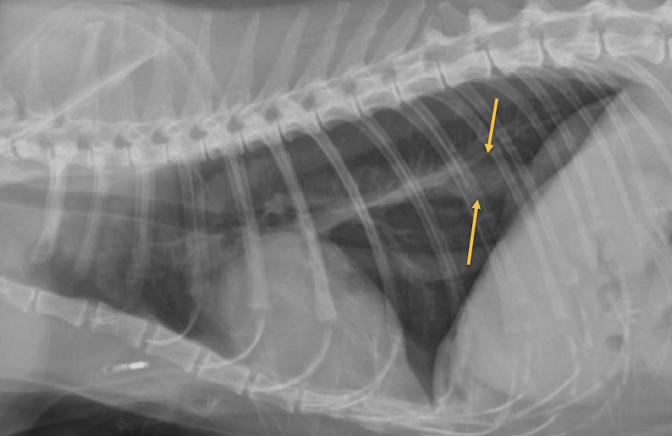

A

Myasthenia gravis with aspiration pneumonia